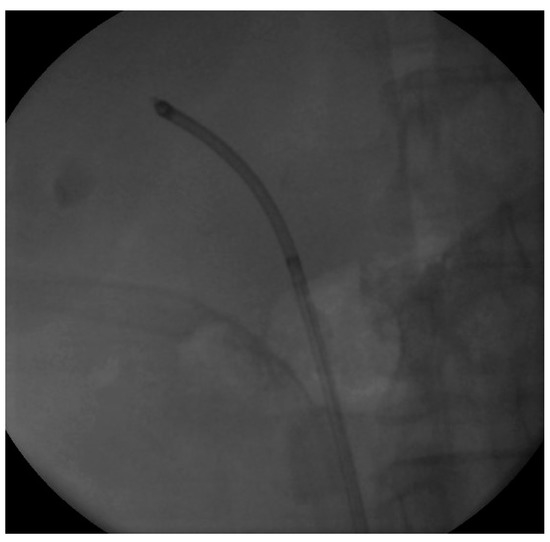

We proceeded with our standardized protocol of RIRS. Under general anesthesia, the patient was placed in the lithotomy position. At first, we performed a cystoscopy of the bladder. We found the right ureteral orifice and placed an ureteral catheter. Via the catheter, contrast agent was infused and, under fluoroscopy, the renal collecting system and the calculi was detected (Figure 1). The insertion of the guidewire followed, an ureteral access sheath was placed and through it we reached the kidney with a flexible ureteroscope of 8.6 French. The stones were found in the upper calyx and in the pelvis (Figure 2) so we began lithotripsy using holmium laser, checking throughout the whole procedure with fluoroscopy. In the meantime, the contrast agent was almost eliminated from the pelvicalyceal system and the stones were efficiently exported. Although we could not see any other calculi in the system, in the fluoroscopy there seemed to be one more (Figure 3). Therefore, we continued our endoscopy in order to find it. We came up to a small aperture in the spot that was indicated to us by the fluoroscopy, so we diagnosed an infundibulum stenosis and thought that the calculi would be within the calyx. The ureteroscope could not be inserted due to the stenosis, so we used the laser to widen the aperture. When the bore was opened and the access to the calyx was provided (Figure 4) we still could not found any calculi. In the fluoroscopy the sign has disappeared (Figure 5) so we understood that the contrast agent was entrapped in the calyx mimicking a stone in the fluoroscopy. The patient was stone free. We placed a double-J stent according to our protocol and the operation has ended. The patient the next day was free to leave the hospital without any complications, according to Clavien–Dildo system.

Figure 2. Endoscopy image of the stone.